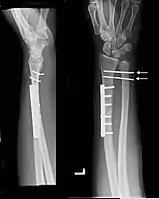

Images

Galeazzi fracture after surgical fixation

Galeazzi fractures are best treated with open reduction of the radius and the distal radio-ulnar joint.[3] It has been called the "fracture of necessity," because it necessitates open surgical treatment in the adult.[4] Nonsurgical treatment results in persistent or recurrent dislocations of the distal ulna.[1] However, in skeletally immature patients such as children, the fracture is typically treated with closed reduction.[1]